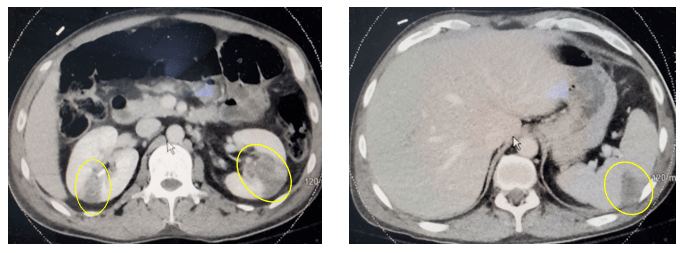

A 40 year old male with a history of cardiomyopathy requiring a left ventricular assist device (LVAD) was seen in clinic with a complaint of pain at the exit site of the LVAD driveline. History is notable for multiple admissions for driveline-associated complications. Despite extensive prior evaluation, cultures and imaging of the driveline exit site had been repeatedly negative with the exception of a methicillin-susceptible Staphylococcus aureus.This was treated with nafcillin, followed by doxycycline for oral suppression. The patient had stopped taking oral antibiotics two months prior to presentation. Imaging revealed a 1.4 cm region around the driveline exit site suggestive of either phlegmon, hematoma, or a developing abscess. Blood cultures and cultures of the driveline exit site were collected and sent to the clinical microbiology laboratory. Upon physical examination, the driveline exit site was tender, but no erythema was noted. The patient endorsed intermittent rust-colored drainage from the site. Blood cultures remained negative for the duration of the patient’s hospital course, and the patient was discharged on nafcillin with plans to transition to doxycycline.